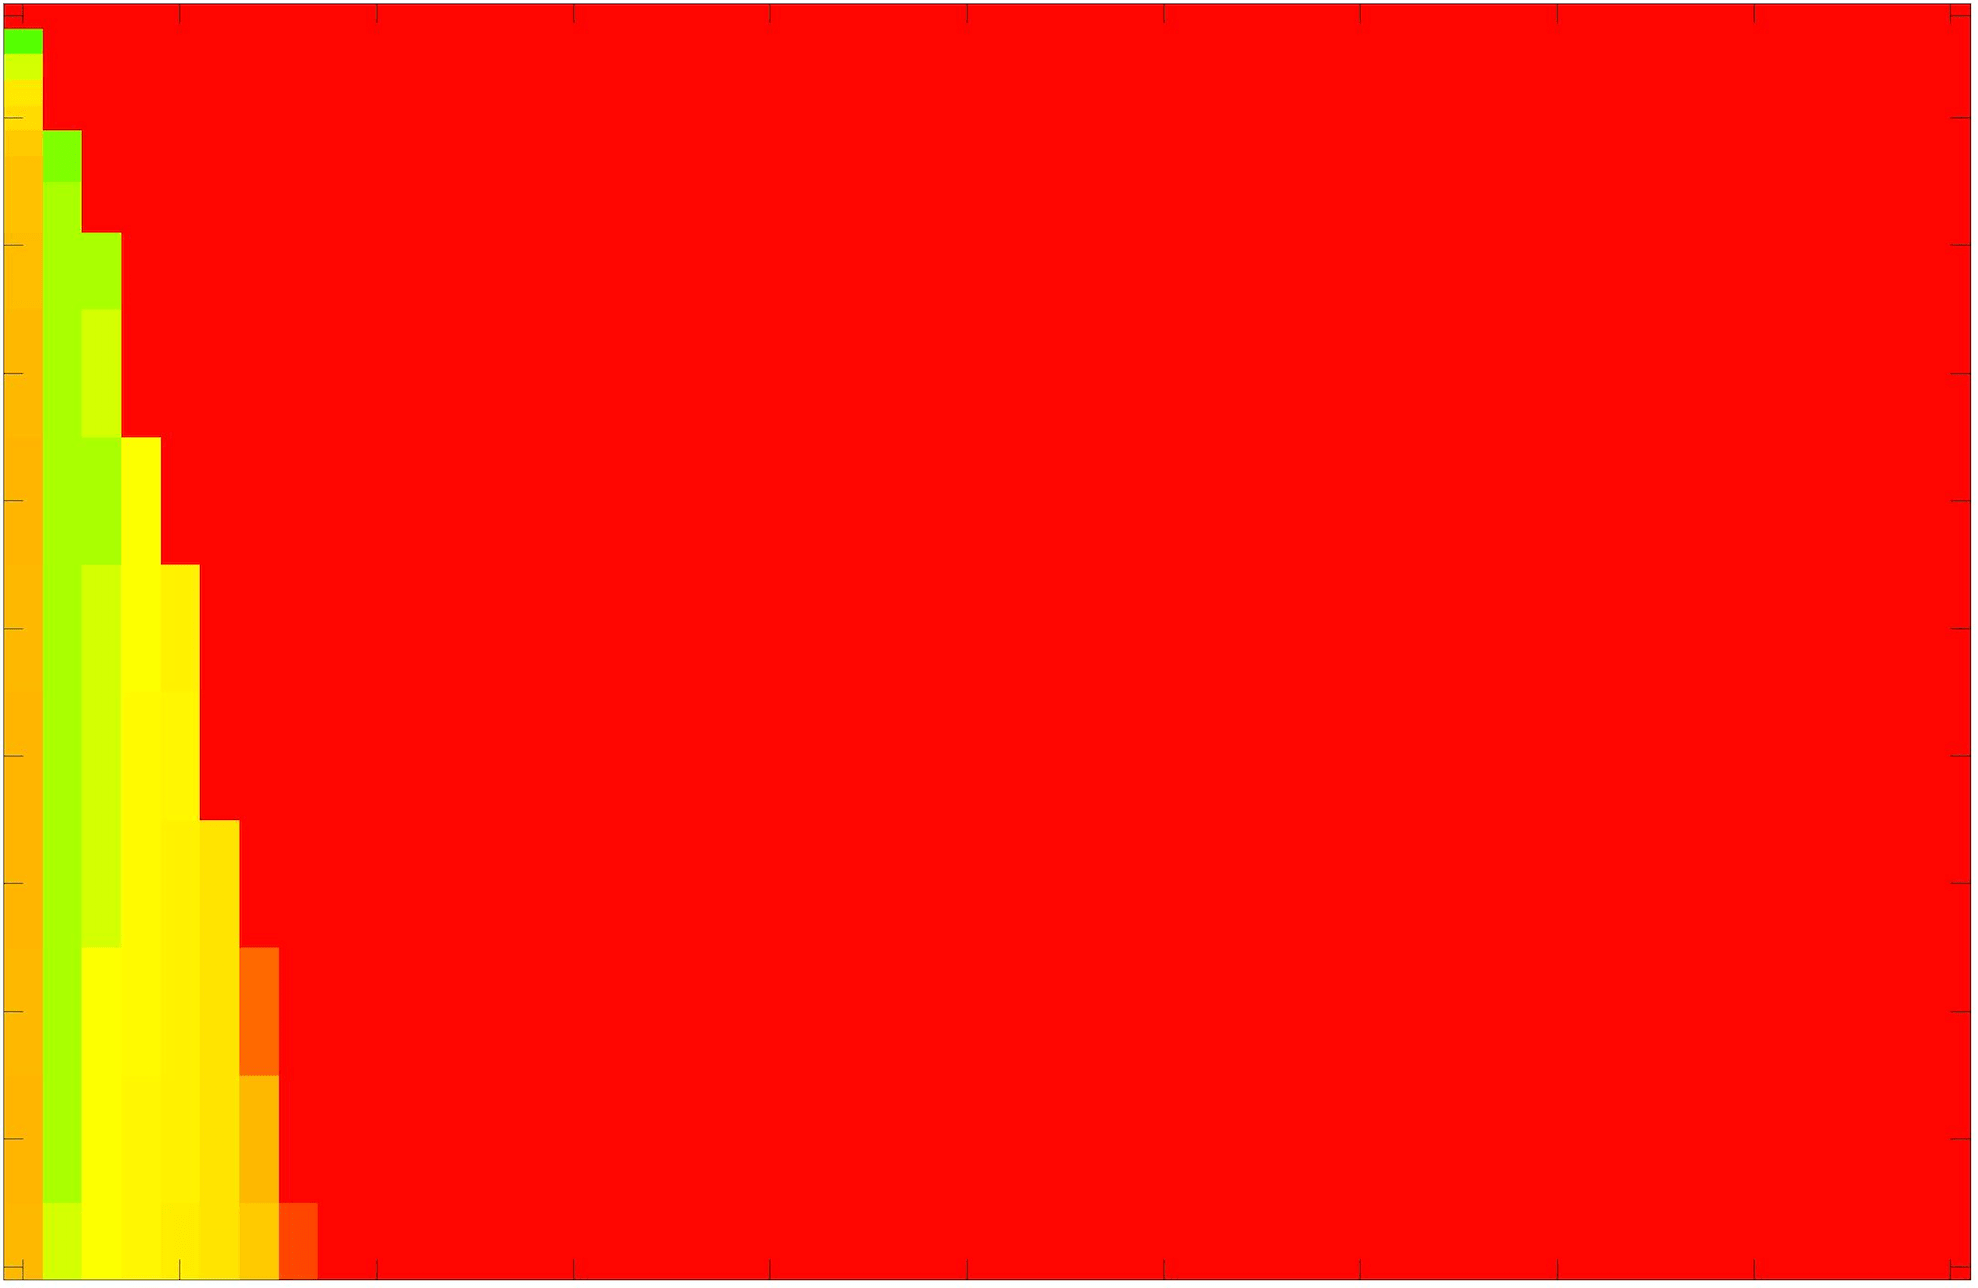

where refers to the number of points in the enclosed region. This takes values in the range , with higher TC values indicating a more accurate segmentation. In the following we will represent accuracy visually from red () to green (), with the intermediate scaling of colours used shown in Fig. 8. This will be particularly relevant in §7.2.

The TC values for the parameter sets are presented as heatmaps in Figs. 11–13. A heatmap is a convenient way to display accuracy results for hundreds of tests concisely. In Fig. 9 we give an example heatmap with the same axes used for those in Figs. 11–13. For each of the combinations of parameter values we give the TC value of the segmentation result and represent it by the appropriate colour. The corresponding colour scale is shown in Fig. 8. Qualitatively, the more green areas of the heatmap the more accurate the model is for a wider set of parameters. Example results for Test Image 5 when varying (with ) for the proposed model are given in Fig. 10. Here it can be seen what each accuracy result corresponds to visually.

Note. The axes have been removed from the heatmaps in Figs. 11–13 for presentational clarity. However, to be explicit, the axes used in all heatmaps are the same as those in Fig. 9.

Synthetic Images. These results are presented in Fig. 11. For Test Images 1–2 we see poor parameter robustness from all competing models, except for GAV which performs reasonably well. However, the proposed model has minimal parameter sensitivity for these images, with good results achieved for almost every combination of values tested. For Test Image 3 all models have a reasonable parameter range (except for RSF), however the proposed model gives better quality results for a wider parameter range. The other models achieve reasonable results here as the foreground intensity of the ground truth is greater than the background , whereas for Test Images 1–2 they are equal . These results highlight the key advantage of the proposed model.

Real Images. In Fig 12 we present results for Test Images 4–6. Here, the proposed model performs in a similar way to its competitors because these images are more typical selective segmentation problems in the sense that there is a clear distinction between the foreground and background intensities. In particular, the values in each case are: Test Image 4 , Test Image 5 , and Test Image 6 . It can be seen that the proposed model is competitive compared to previous approaches. The performance is quite poor for Test Image 5, but is arguably still the best for this challenging case. In Fig. 13 we present results for Test Images 7–9. Here the proposed model outperforms previous approaches significantly for each image. This is mainly due to the type of image considered. Specifically, the true intensities are: Test Image 7 , Test Image 8 , and Test Image 9 . The proposed model is capable of achieving results where , with other models failing completely in these cases.